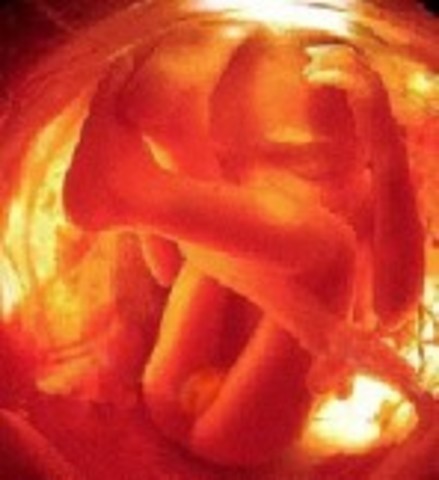

• Week 9: Phalanges

Week 9: Phalanges

The embryo is now at 30 mm. Cartilage and bones are developing, as are finger and toes starting to take their shape. Facial features such as the tongue and upper lip are being identifed with the embryo. The heart is now fully developed. The head is beginning to enlarge in size due to rapid growth of the brain.

Facts:During this week of pregnancy your baby is now swimming round in a little bag of fluid

-During this week, the baby's veins are clearly visible